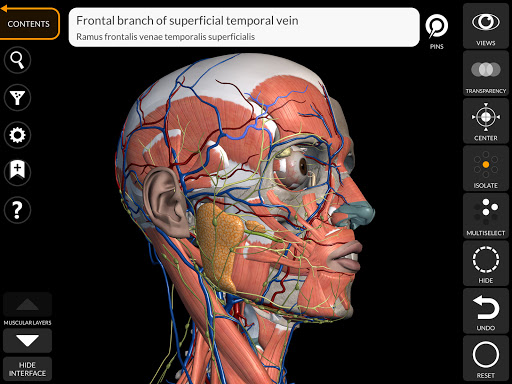

"Anatomy 3D Atlas" memungkinkan Anda mempelajari anatomi manusia dengan cara yang mudah dan interaktif.

Melalui antarmuka yang sederhana dan intuitif, Anda dapat mengamati setiap struktur anatomi dari sudut mana pun.

Model 3D anatomi sangat terperinci dan memiliki tekstur hingga resolusi 4k.

Pembagian berdasarkan wilayah dan tampilan yang telah ditetapkan sebelumnya memudahkan pengamatan dan studi bagian tunggal atau kelompok sistem dan hubungan antara organ yang berbeda.

saraf • Sistem pernapasan • Sistem pencernaan • Sistem urogenital (pria dan wanita) • Sistem endokrin • Sistem limfatik • Sistem mata dan telinga FITUR • Antarmuka yang sederhana dan intuitif • Putar dan perbesar setiap model dalam ruang 3D • Opsi untuk menyembunyikan atau mengisolasi satu atau beberapa model yang dipilih • Filter untuk menyembunyikan atau menampilkan setiap sistem • Fungsi pencarian untuk menemukan setiap bagian anatomi dengan mudah • Fungsi penanda untuk menyimpan tampilan khusus • Rotasi cerdas yang menggerakkan pusat rotasi secara otomatis • Fungsi transparansi • Visualisasi otot melalui tingkat lapisan dari yang superfisial hingga yang terdalam • Dengan memilih model atau pin, istilah anatomi terkait akan muncul • Deskripsi otot: asal, • Tampilkan/ Sembunyikan antarmuka UI (sangat berguna dengan layar kecil) MULTIBAHASA • Istilah anatomi dan antarmuka pengguna tersedia dalam 11 bahasa: Latin, Inggris, Prancis, Jerman, Italia, Portugis, Turki, Rusia, Spanyol, Mandarin, Jepang, dan Korea • Istilah anatomi dapat ditampilkan dalam dua bahasa secara bersamaan PERSYARATAN SISTEM • Android 8.0 atau yang lebih baru, perangkat dengan RAM minimal 3GB Reversi